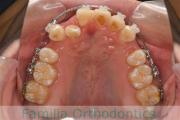

でこぼこと口元が出ている横顔が気になるとのことで来院されました。重度の叢生(ガタガタ)と側方へのズレがあるため、アンカースクリューを併用したマルチブラケット法にて治療を行いました。3年弱、35回程度の通院をしていただきました。叢生が強いため、部分的にガタガタが再発・後戻りするリスクが高いケースでした。

- ≫治療前

上顎

下顎

- ≫治療後